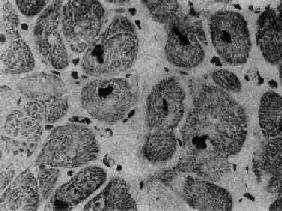

图8-36 肥厚性心肌病 心肌细胞肥大,核大浓染 (采自Edwards)

图8-35 肥厚性心肌病 心室横断面(上面观),左心室腔缩小,心室壁均匀增厚,整个心肌布满白色纤维化区,室间隔与后壁厚度之比仅稍大于正常值(1.4) 镜下,心肌细胞显著肥大,核大而浓染(图8-36),核周有亮区包围,组织化学染色证明为糖原堆积,具有一定的诊断意义。心肌细胞排列紊乱较其它型心肌病为甚,而且常呈旋涡状或缠绕呈簇状排列(图8-37),细胞内肌原纤维不呈平行排列,而是向各个方向、互相交错排列。常有间质纤维化灶形成,但以内膜纤维化,尤其位于主动脉瓣下区的内膜纤维化为突出。位于肥厚的室间隔内的冠状动脉分支管壁常有增厚现象。